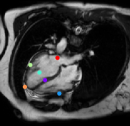

Datasets: A set of isotropic mm MR scans were obtained from the ADNI database [10] to evaluate the proposed method. While, a subset of and images are used for training and testing. All brain images were skull stripped and affinely aligned to the MNI space, thus allowing ground truth planes to be extracted in the standard directions. For cardiac images, we use short-axis cardiac MR of resolution mm obtained from the UK Digital Heart Project [8]. A subset of and images are used for training and testing. ACPC planes are evaluated using the AC and PC landmarks for the distance error calculation. Similarly, we use the outer aspect, inferior tip and inner aspect points of splenium of corpus callosum for mid-sagittal planes. For cardiac MRI, we use six landmarks projected on the 4-chamber plane; the two right ventricle (RV) insertion points, right and left ventricles (LV) lateral wall turning points, apex, and the center of the mitral valve, See Fig. 2.

Results: During inference, the environment samples a plane and the agent updates sequentially new plane’s parameters until reaching the terminal state. In order to have a fair comparison between different variants of the proposed method, we fix the initial plane for all models during evaluation. Table 1 shows the results from these comparative experiments. All methods share similar performance including speed and accuracy, and there is no unique winner for the best overall method. Best performing agents for detecting the mid-sagittal and ACPC planes achieve accuracy of mm and , and mm and , respectively. Where in cardiac, the task is more complex due to the lower quality and higher variability between different scans. The agent has to navigate in a bigger field of view compared to brain images. Thus Duel DQN-based architectures achieve the best results for detecting the 4-chamber plane with mm and accuracy, as a result from learning a better state value function by decoupling it from action-value function. These results are better than the state-of-the-art [6], which achieves an accuracy of mm and . Unlike [6], our method does not require manual annotation of landmarks. More visualization results are published on our github.